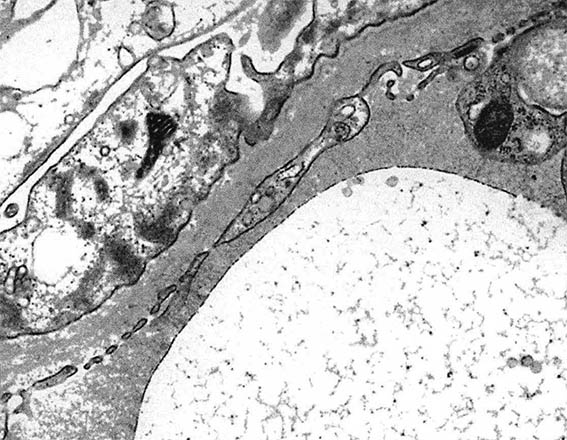

El estudio de microscopía electrónica demostró engrosamiento irregular de la MBG, con multilaminación y fragmentación de la lámina densa (Figura 16).

Figura 16. Microscopía electrónica mostrando engrosamiento irregular de la MBG, multilaminación y fragmentación de la lámina densa (X 6,000).